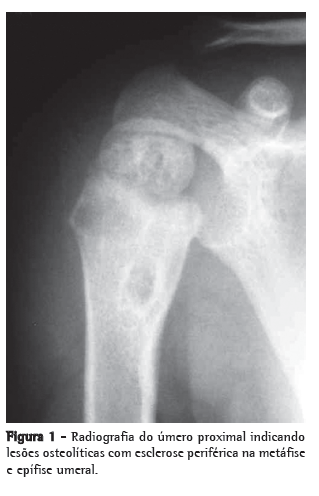

Os exames subsidiários mostraram hemograma com 8.200 leucócitos (9 bastões e 66 neutrófilos); velocidade de hemossedimentação de 32 mm na primeira hora, proteína C reativa < 6,0 mg/L; sedimento urinário normal; radiografia de tórax normal; e PPD positivo reator forte, com 18 mm. A TC de úmero mostrou múltiplas lesões líticas na região proximal do úmero, envolvendo a epífise, a metáfise e a diáfise proximal, com descontinuidade cortical e edema de tecidos moles adjacentes (Figura 3).

Lesões líticas e escleróticas ósseas com reação periosteal caracterizam as lesões radiográficas. Os achados de TC na epífise, na metáfise e na diáfise foram consistentes com a descrição prévia em pacientes jovens.

Crianças mais velhas geralmente apresentam apenas alterações metafisárias.(4)